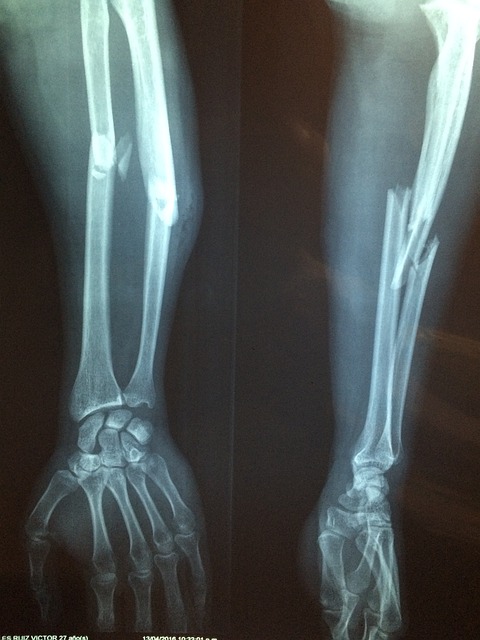

연골은 관절을 보호하는 부드러운 조직으로, 관절의 원활한 움직임을 돕고 충격을 흡수합니다. 연령 증가, 부상, 또는 특정 건강 상태로 인해 연골이 손상되거나 마모될 수 있으며, 콘드로이친은 이러한 연골의 손상을 늦추거나 관절 건강을 개선하는 데 도움을 줄 수 있습니다.